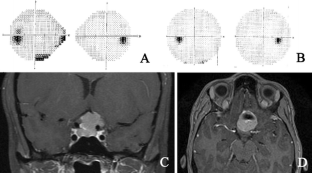

Fig. 1